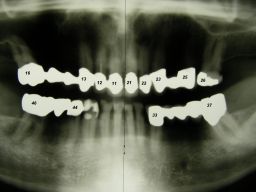

Das etwas dunkle Röntgenbild links(6/2003) zeigt diverse Probleme. Hier interessiert, daß der Zahn 22 (sprich: "zwei", "zwei") am 28.10.05 Schmerzen bereitete, weil der Zahnnerv unter Eiterbildung abgestorben war. Es brauchte 3 medikamentöse Einlagen, bis der Zahn ruhig war und am 18.11.05 eine Wurzelfüllung und einen Titanstift in den Wurzelkanal bekommen konnte. Bei der anschließenden Röntgenkontrolle rechts fiel der schlechte Randschluß der Krone 22 auf.